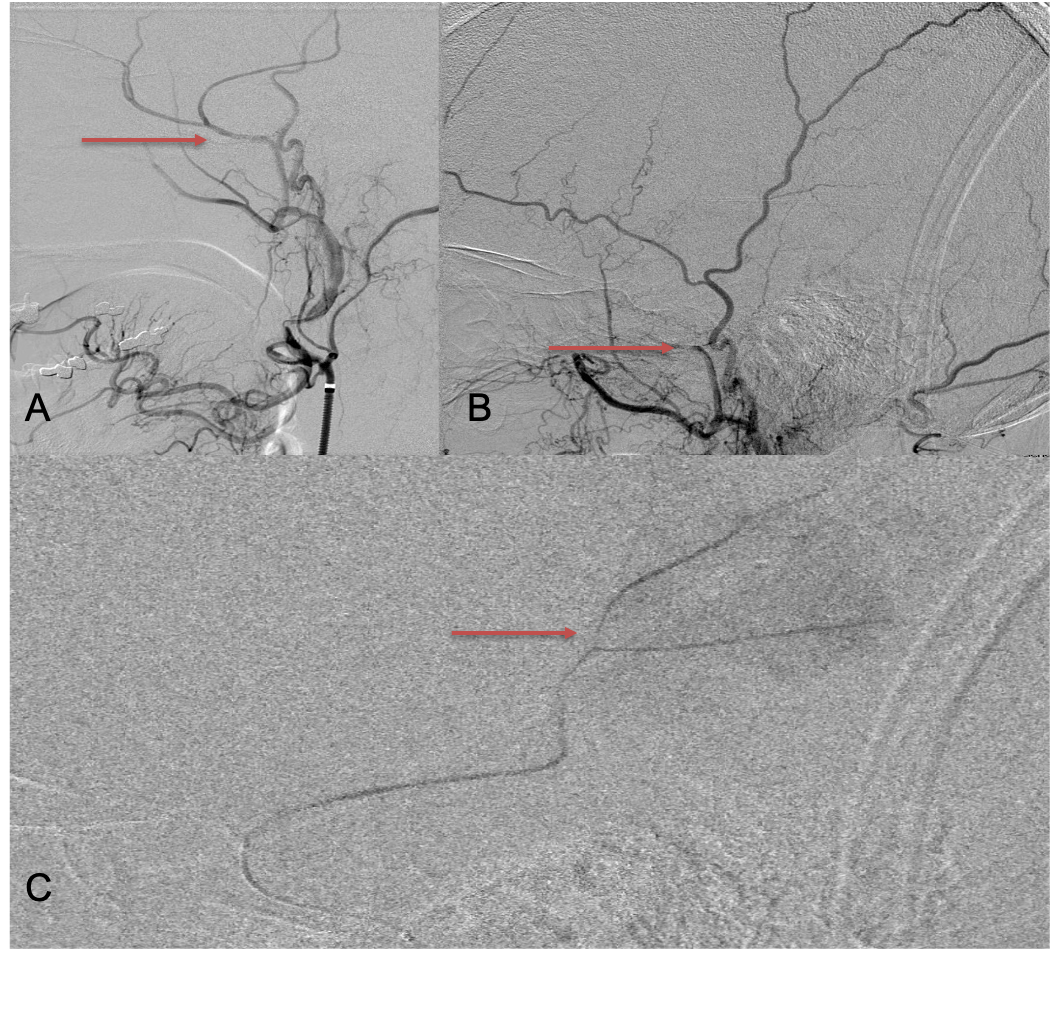

CT follow-up at 1 week demonstrates early resorption. 2 weeks post MMA embolization, resolution of the left subdural collection with new small thin acute hemorrhage in an otherwise stable right subdural collection is observed (Figure 3. A and B).

Figure 3. A) 1 week post MMA embolization demonstrating decreasing thickness bilaterally B) 2 weeks post MMA demonstrates resolution on left, with small new acute component on right with overall decreased thickness.